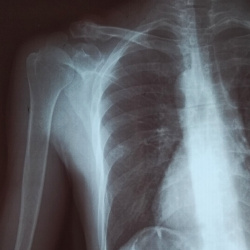

Женщина 1991 г р. Проходила флг, доктор увидел в плечевой кости доп.тень отправил на рг. доктора подскажите пожалуйста что это может быть?